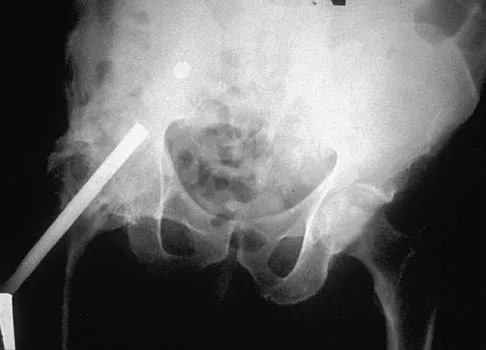

Figures 10a through 10c show the plain radiograph and MRI scans of a 41-year-old man who has right hip pain. What is the most likely diagnosis?

Explanation

Transient osteoporosis is a self-limited painful but reversible disorder. Although first described in pregnant women, it is more common in young to middle-aged men. The radiograph shows loss of mineralization in the right hip relative to the left side. There is no osseous destruction or cortical expansion typical of metastasis or giant cell tumor. The process is confined to the femoral side of the joint unlike rheumatoid arthritis, which would be centered in the joint. Osteonecrosis is better defined with sharp but irregularly shaped margins, and there is no double-line sign. The MRI scans reveal diffuse edema in the femoral head and neck that is atypical for osteonecrosis. Transient osteoporosis may recur in the same or opposite hip.